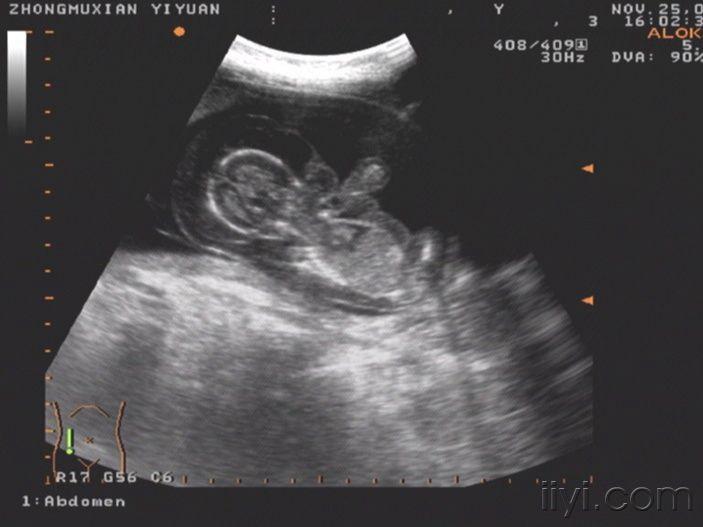

这个胎儿穿上了“太空衣”(典型胎儿水肿图片,值得分享!)

一位32岁经产妇,孕20周前来检查,发现胎儿被一层透明的膜状物包绕,从头颅到肢体,考虑胎儿水肿综合症!